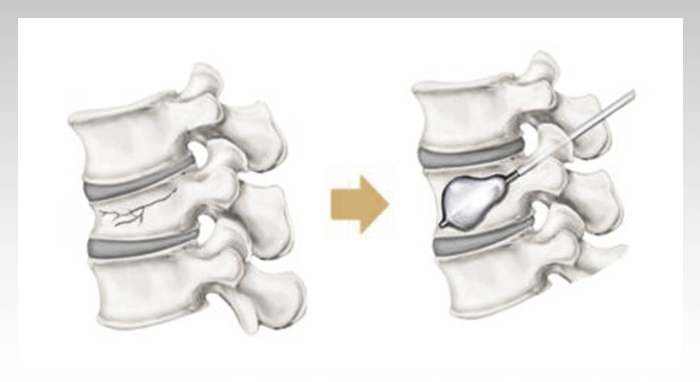

가느다란 관을 이용해 부러진 척추골 속으로 바늘을 삽입한 후, 골시멘트를 주입하여 단단히 굳히는 시술입니다. 상황에 따라서 풍선을 넣고 부풀려서 무너진 척추체를 높인 후 골시멘트를 주입하는** '풍선척추성형술'**을 시행하기도 합니다.